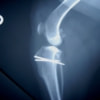

■ 症例20 ポメラニアン 8ヶ月 1.8kg

左右膝蓋骨脱臼 グレードⅢ

2ヶ月前から間欠的跛行が認められ、両膝の膝蓋骨脱臼整復術を行った。

手技は縫工筋及び内側広筋の解放、脛骨粗面の外側転位、滑車ブロック形造溝術、内外側関節包の縫縮を選択し実施した。

右側の膝蓋骨脱臼は上記手技で整復されたものの、左側はそれのみでは膝蓋骨が浮く様子が認められた。その為、PDS縫合糸にて膝蓋靱帯を1糸のみ縫合し、靱帯の縫縮を行った。

膝蓋骨脱臼は膝関節における膝蓋骨の内外側の脱臼と定義されるが、時として単純な内外の脱臼ではなく、膝蓋骨が大きく前方に浮き上がるように脱臼する場合がある。特にトイプードルやポメラニアンといった犬種に多く認められる。

内側脱臼に加えて前方への浮き上がりを矯正する為に、従来より脛骨粗面転移により膝蓋靭帯を外方と下方に引っ張り、固定する方法を選択する。膝蓋骨の前方への浮き上がりが軽度の場合は、従来法ではなく関節包の縫縮で対応していた。しかし、一部の症例で膝蓋骨の動きが悪くなり伸展機構が円滑に機能せずロボット様歩行になるケースがあった。

その為、膝蓋靭帯自体を縫縮する方法を採用した。この方法により、膝関節の伸展機構を妨げず膝蓋骨の軽度の浮きを矯正することが可能となった。

本症例の経過は良好である